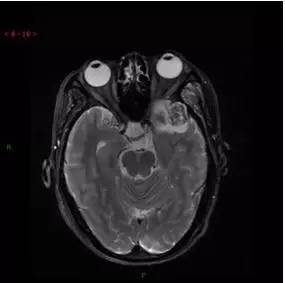

T2WI/FS轴位

解析:本病例为中颅窝至颞下窝沟通性病变,对周围骨质主要呈膨胀压迫性改变,伴囊变、出血。

病理:(中颅底内外沟通肿瘤) 神经鞘瘤,伴出血,局灶细胞较丰富。免疫组化结果显示:EMA(-), P53(-), S100(3 ), NF(-), PR(-), desmin(-), Ki-67( ,5-10%)

神经鞘瘤